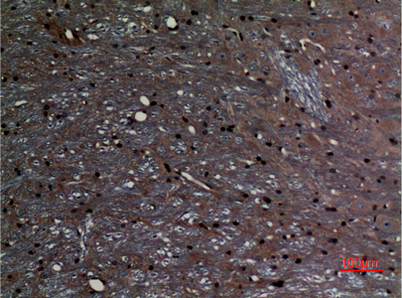

Product name: ABCG1 rabbit pAb

Dilutions: Western Blot: 1/500 - 1/2000. IHC-p: 1:100-300 ELISA: 1/10000. Not yet tested in other applications.

Immunogen: Synthesized peptide derived from ABCG1 . at AA range: 560-640